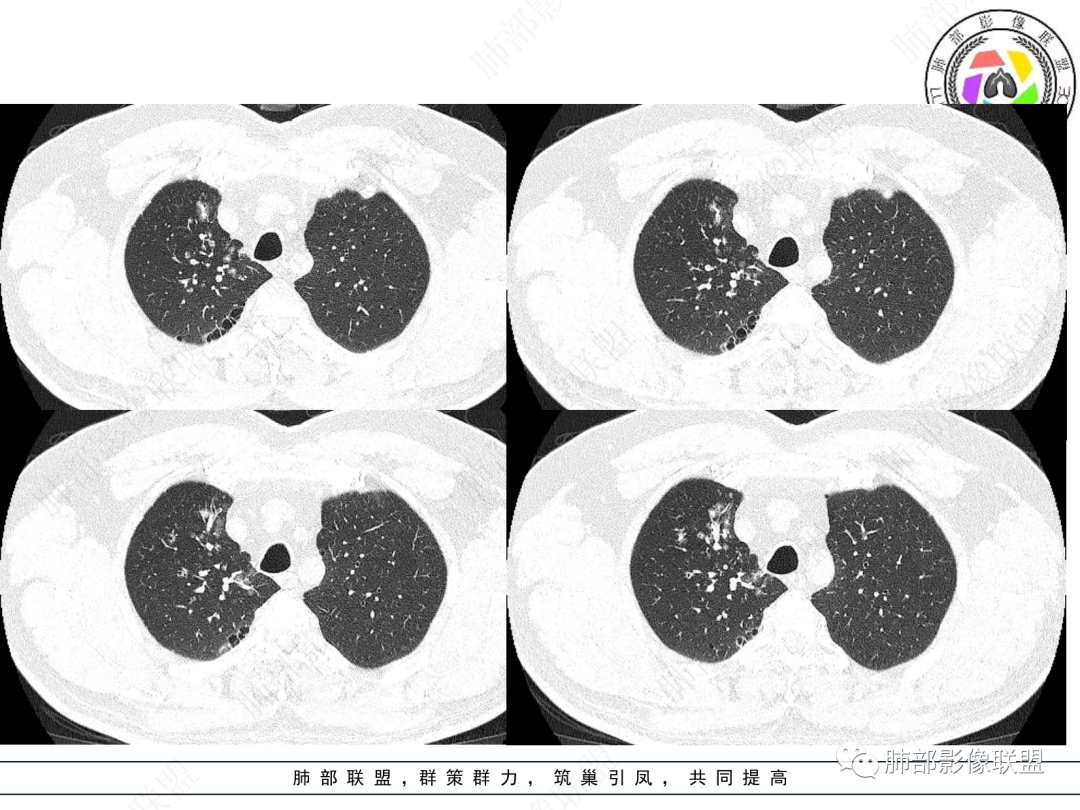

右肺上叶支气管截断,内见软组织密度结节,支气管管壁破坏,病变侵及管外,增强强化明显。右肺上叶沿气管血管束多发斑片影,考虑恶性性病变并阻塞性炎症,鳞癌,神经内分泌肿瘤。

右主支气管及肺门不规则软组织结节,点状钙化,不均匀强化,气管壁破坏,上叶支气管阻塞,分支粘液栓,血管束增粗,沿支气管分布多发结节,考虑鳞癌合并阻塞性炎症,鉴别结核。

男,52。间断咳嗽、咳痰2周,加重3天。胸部CT:右主、右上叶支气管多发软组织影,跳跃不连续,内可见小环状高密度,点状钙化,管壁破坏,上叶支气管堵塞,远端分支粘液栓,可见小支气管管壁增厚、管腔狭窄,沿支气管分布多发结节,无大片炎症不张。考虑:TB?NTM?鉴别Ca并阻塞性炎症。

右肺上叶支气管开口见阻塞物影及强化,息肉样向腔内外浸润性生长,并有颗粒钙化,右肺上叶段支气管主干增粗及密度增高,见指套征,支气管血管旁见多发小斑点,小斑片影阻塞性炎性病灶〈小花小草表现〉,支气管镜示新生物血供丰富(结核完全排除),方向恶性,符合鳞癌特点,与小细胞Ca鉴定,临床专科支气管镜取材活检明确诊断。

腔内肿物,强化不均匀,强化程度为轻中度强化(CT值增加25HU),且强化特点为快进快出,右肺上叶支气管责任区域的阻塞性炎症加痰栓(气管镜也证实右上叶支气管内痰多)。这些均明确指向鳞癌。

一点不异常啊,分布在阻塞责任气管区域的支气管增粗伴腺泡结节(细支气管腔内及肺泡内阻塞性炎症伴痰栓),只不过还没有大片实变而已。@韩平     临沂市人民医院呼吸科

这个病例比较好,我们的观察点在哪?这是右上叶支气管病变,需要了解:腔内、壁、腔外、远端,腔内有软组织密度影,近端膨隆。

影像上分析的观察点:腔内、壁、腔外、远端,然后就是远端肺组织、淋巴结、肺血管、胸膜、其他肺部,这个人就是阻塞性炎症为主。